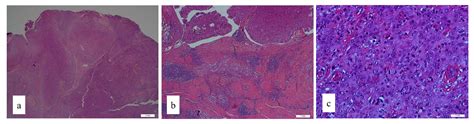

The Scrotal Excision of Paratesticular Mesothelioma of the Tunica ...